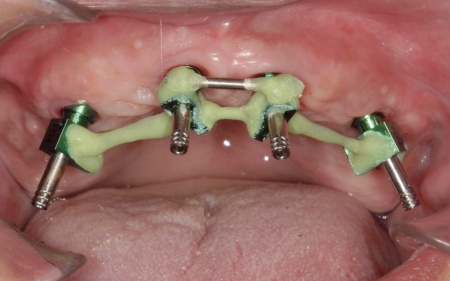

①上の歯7本、右下の奥歯2本を抜歯する。上あごには抜歯と同時に4本のインプラントを埋め、その上に10本分の仮歯を取り付けるオールオンフォーを行う。

インプラントの種類には、あごの骨と結合する力に優れたオステム社のETⅢを採用。インプラントが骨にしっかり定着するまでの間は、通常のインプラントよりも細い暫間インプラントを一時的に併用して仮歯を支える